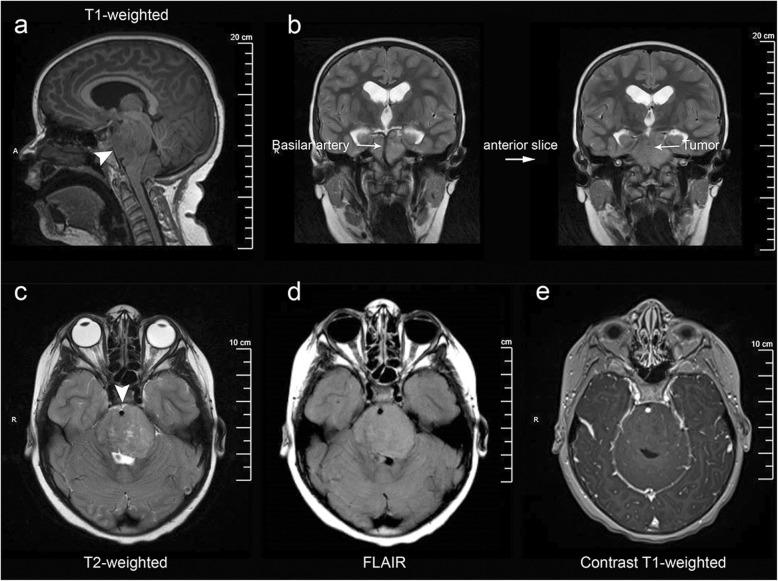

Diffuse intrinsic pontine glioma-like tumor with EZHIP expression and molecular features of PFA ependymoma.

Acta Neuropathol Commun. 2020 Mar 20;8(1):37. doi: 10.1186/s40478-020-00905-w.

DOI:10.1186/s40478-020-00905-w

PMID:32197665

原文链接:https://pmc.ncbi.nlm.nih.gov/articles/PMC7083001/